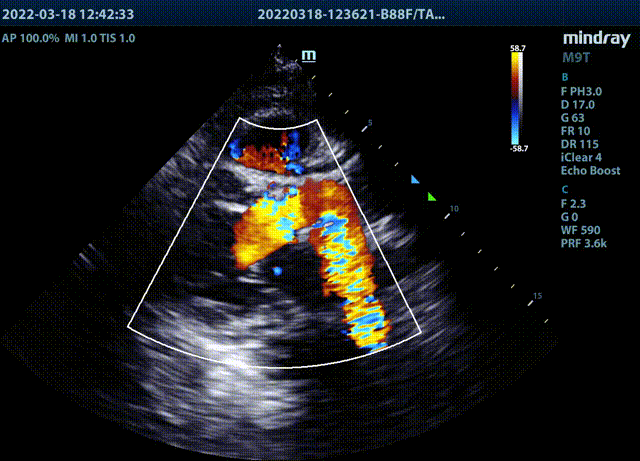

超声检查

彩超证实王女士的确存在重度主动脉狭窄合并轻-中度主动脉瓣关闭不全,且主动脉瓣跨瓣压差高达74mmHg。高度狭窄的主动脉瓣,导致王女士心脏左心室射血到主动脉的过程受阻,久而久之造成心力衰竭。